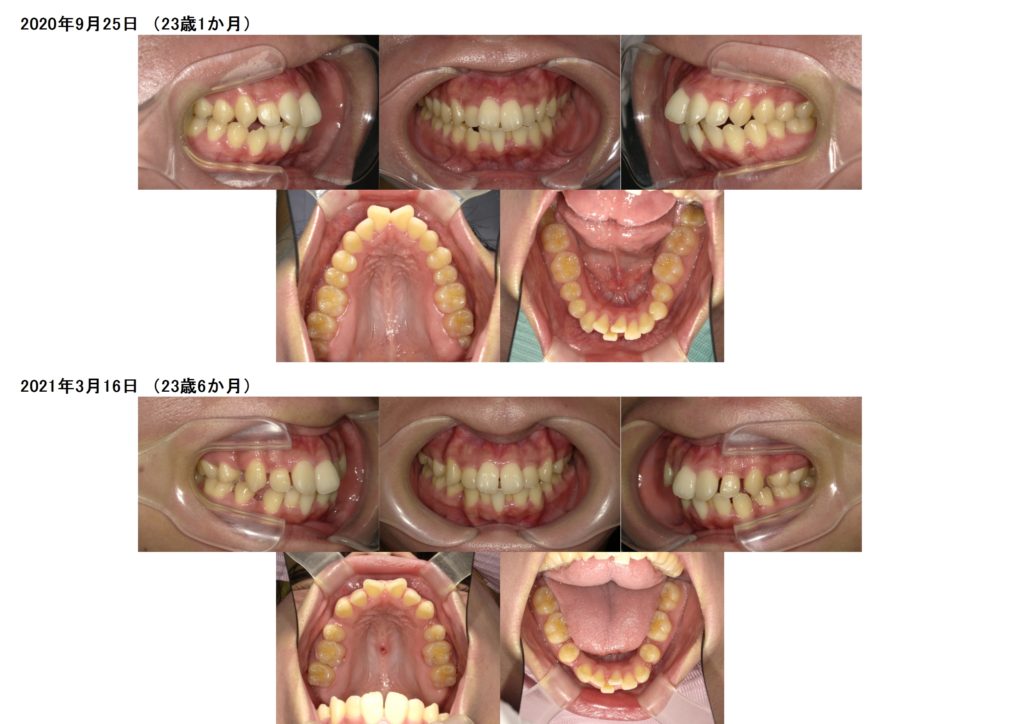

今回はマウスピースでの矯正治療をされた患者さまの治療例です。

上下4番目の歯を抜歯して治療をしました。

少しずつですが確実に前歯も引っ込み、ガタガタ歯並びも治っていますよね。

5カ月ぐらいで噛み合わせも安定しキッチリと並びました。

治療前、治療後の口腔内写真です。

お口元も引っ込み、ガタガタ歯並びも治りました。

横顔もとっても変わりましたよ☆